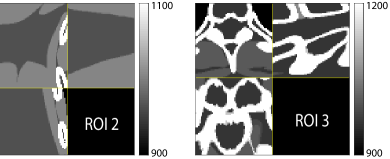

Figure 5: 3D displays of reconstructions of ROI 1 defined in Fig. 4. The display windows are [900, 1200] HU.

Fig. 4 shows the reconstructed images and the corresponding error images for PWLS-EP, PWLS-ULTRA, and SPULTRA, at I0=3×103subscript𝐼03superscript103I_{0}=3\times 10^{3} and I0=2×103subscript𝐼02superscript103I_{0}=2\times 10^{3}. Compared to the PWLS-EP result, both PWLS-ULTRA and SPULTRA achieved significant improvements in image quality in terms of sharper reconstructions of anatomical structures such as bones and soft tissues, and suppressing the noise. However, the PWLS-ULTRA method introduces bias in the reconstructions, which leads to larger reconstruction errors compared to the proposed SPULTRA method. In Fig. 4, we marked three 3D ROIs in the axial plane, i.e., ROI 1, ROI 2, and ROI 3. Fig. 5 shows the zoom-in images of a 3D plot of ROI 1, and those of ROI 2 and ROI 3 are shown in the supplement. We also plot the evolution of RMSE through the axial slices of the three 3D ROIs in Fig. 6. The figures demonstrate that SPULTRA clearly outperforms the competing PWLS-EP and PWLS-ULTRA schemes.

Figure 6: RMSE (HU) for each axial slice of the 3D ROIs (ROI 1, ROI 2, and ROI 3). The X-axis shows slice indices of the central 64 out of 96 axial slices. Left plot: I0=3×103subscript𝐼03superscript103I_{0}=3\times 10^{3}. Right plot: I0=2×103subscript𝐼02superscript103I_{0}=2\times 10^{3}.